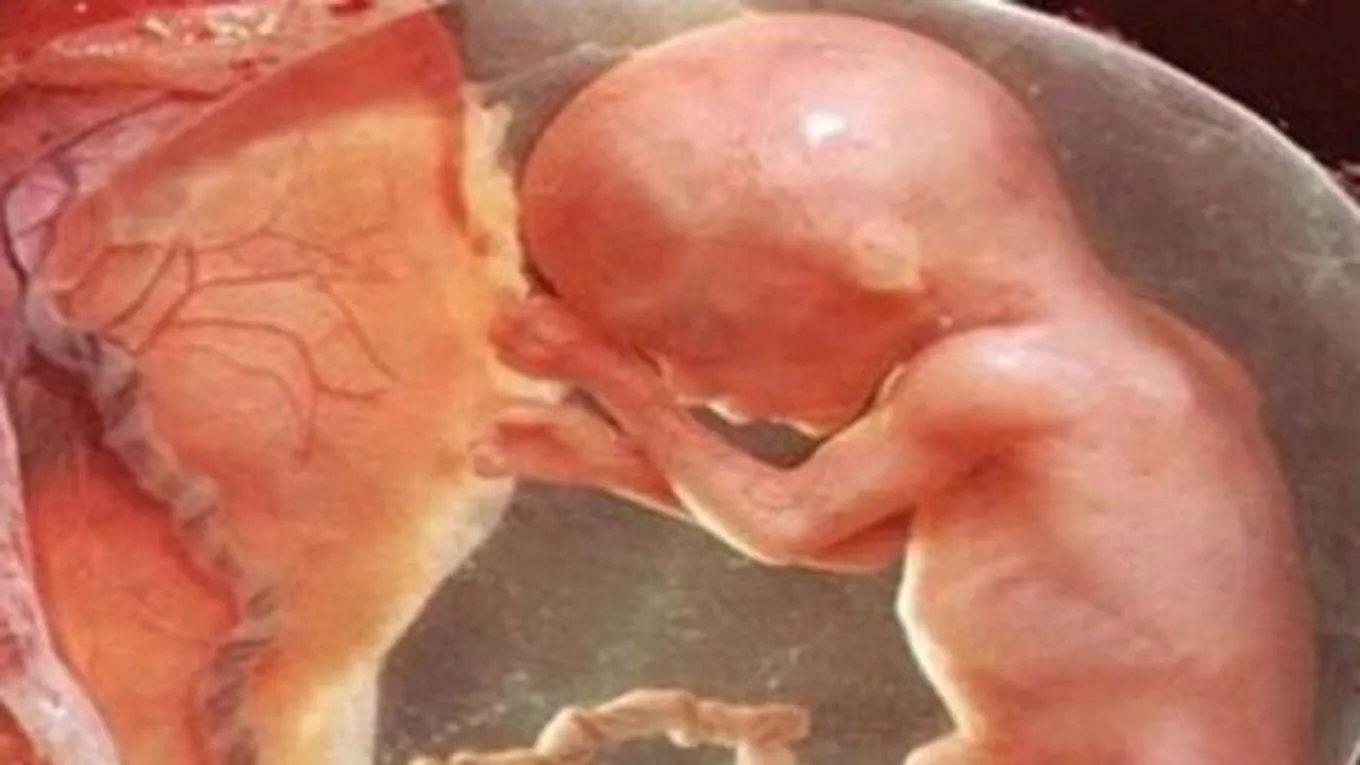

يستمر وزنه بالزيادة ليصل إلى حوالي 100 غم، وطوله سيتجاوز الـ 11 سم، وهنا سيبدأ الطفل بالإحساس أكثر بمحيطه، ويبدأ بالحركة، وشدّ الحبل السرّي، وقد تشعر الأم بألم أو وخز في جوانبها.

وزن الجنين سيصبح 140 غم، وطوله حوالي الـ 13 سم، سيبدأ قلبه بالنبض، وستتمكّن الأم من سماع النبضات عند توججها إلى الطبيب، كما وأنّه خلال هذا الأسبوع، سيبدأ هيكله العظمي بالتماساك، وستختفي الغضاريف التي كانت موجودة بالبداية، وسيبدأ سائل بروتيني ودهني يسمى "الميلين" بتغليف الحبل الشوكي، ومن الضروري في هذا الشهر أن تقوم الأم بعمل فحص للتأكد من خُلو الجنين من أي خلل جنسي أو جيني.